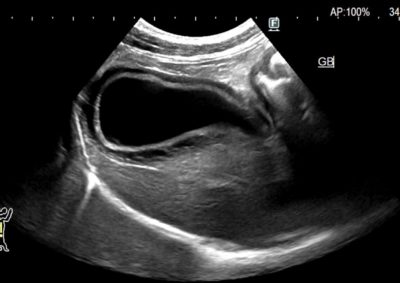

胆嚢破裂に対する胆嚢摘出術〜空腸栄養カテーテル設置